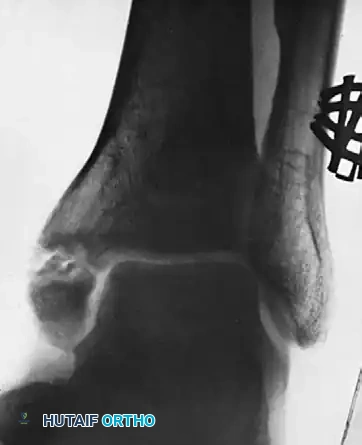

Figure B: Illustrates the ultimate failure of the grafting procedure. Due to persistent pain and lack of osseous integration, the decision was made to proceed with surgical resection. The ununited medial malleolar fragment was carefully excised, ensuring that the deep deltoid ligament was reattached to the remaining stable tibial metaphysis to prevent lateral talar subluxation.

FIGURE 59-17 B, Failure of grafting procedure. Medial malleolus was resected.

Figure C: Represents the long-term follow-up, seven years post-resection. The ankle mortise remains remarkably stable without evidence of talar shift. While mild arthritic changes (joint space narrowing and subchondral sclerosis) are becoming evident, the patient maintains functional mobility. This radiograph highlights a critical biomechanical threshold: this represents the maximal amount of the medial malleolus that can be safely removed while still preserving the intrinsic stability of the ankle joint.

FIGURE 59-17 C, Seven years after resection, ankle is stable, although mild arthritic changes are becoming evident. This is maximal amount of medial malleolus that can be removed if stability of ankle is to be preserved.